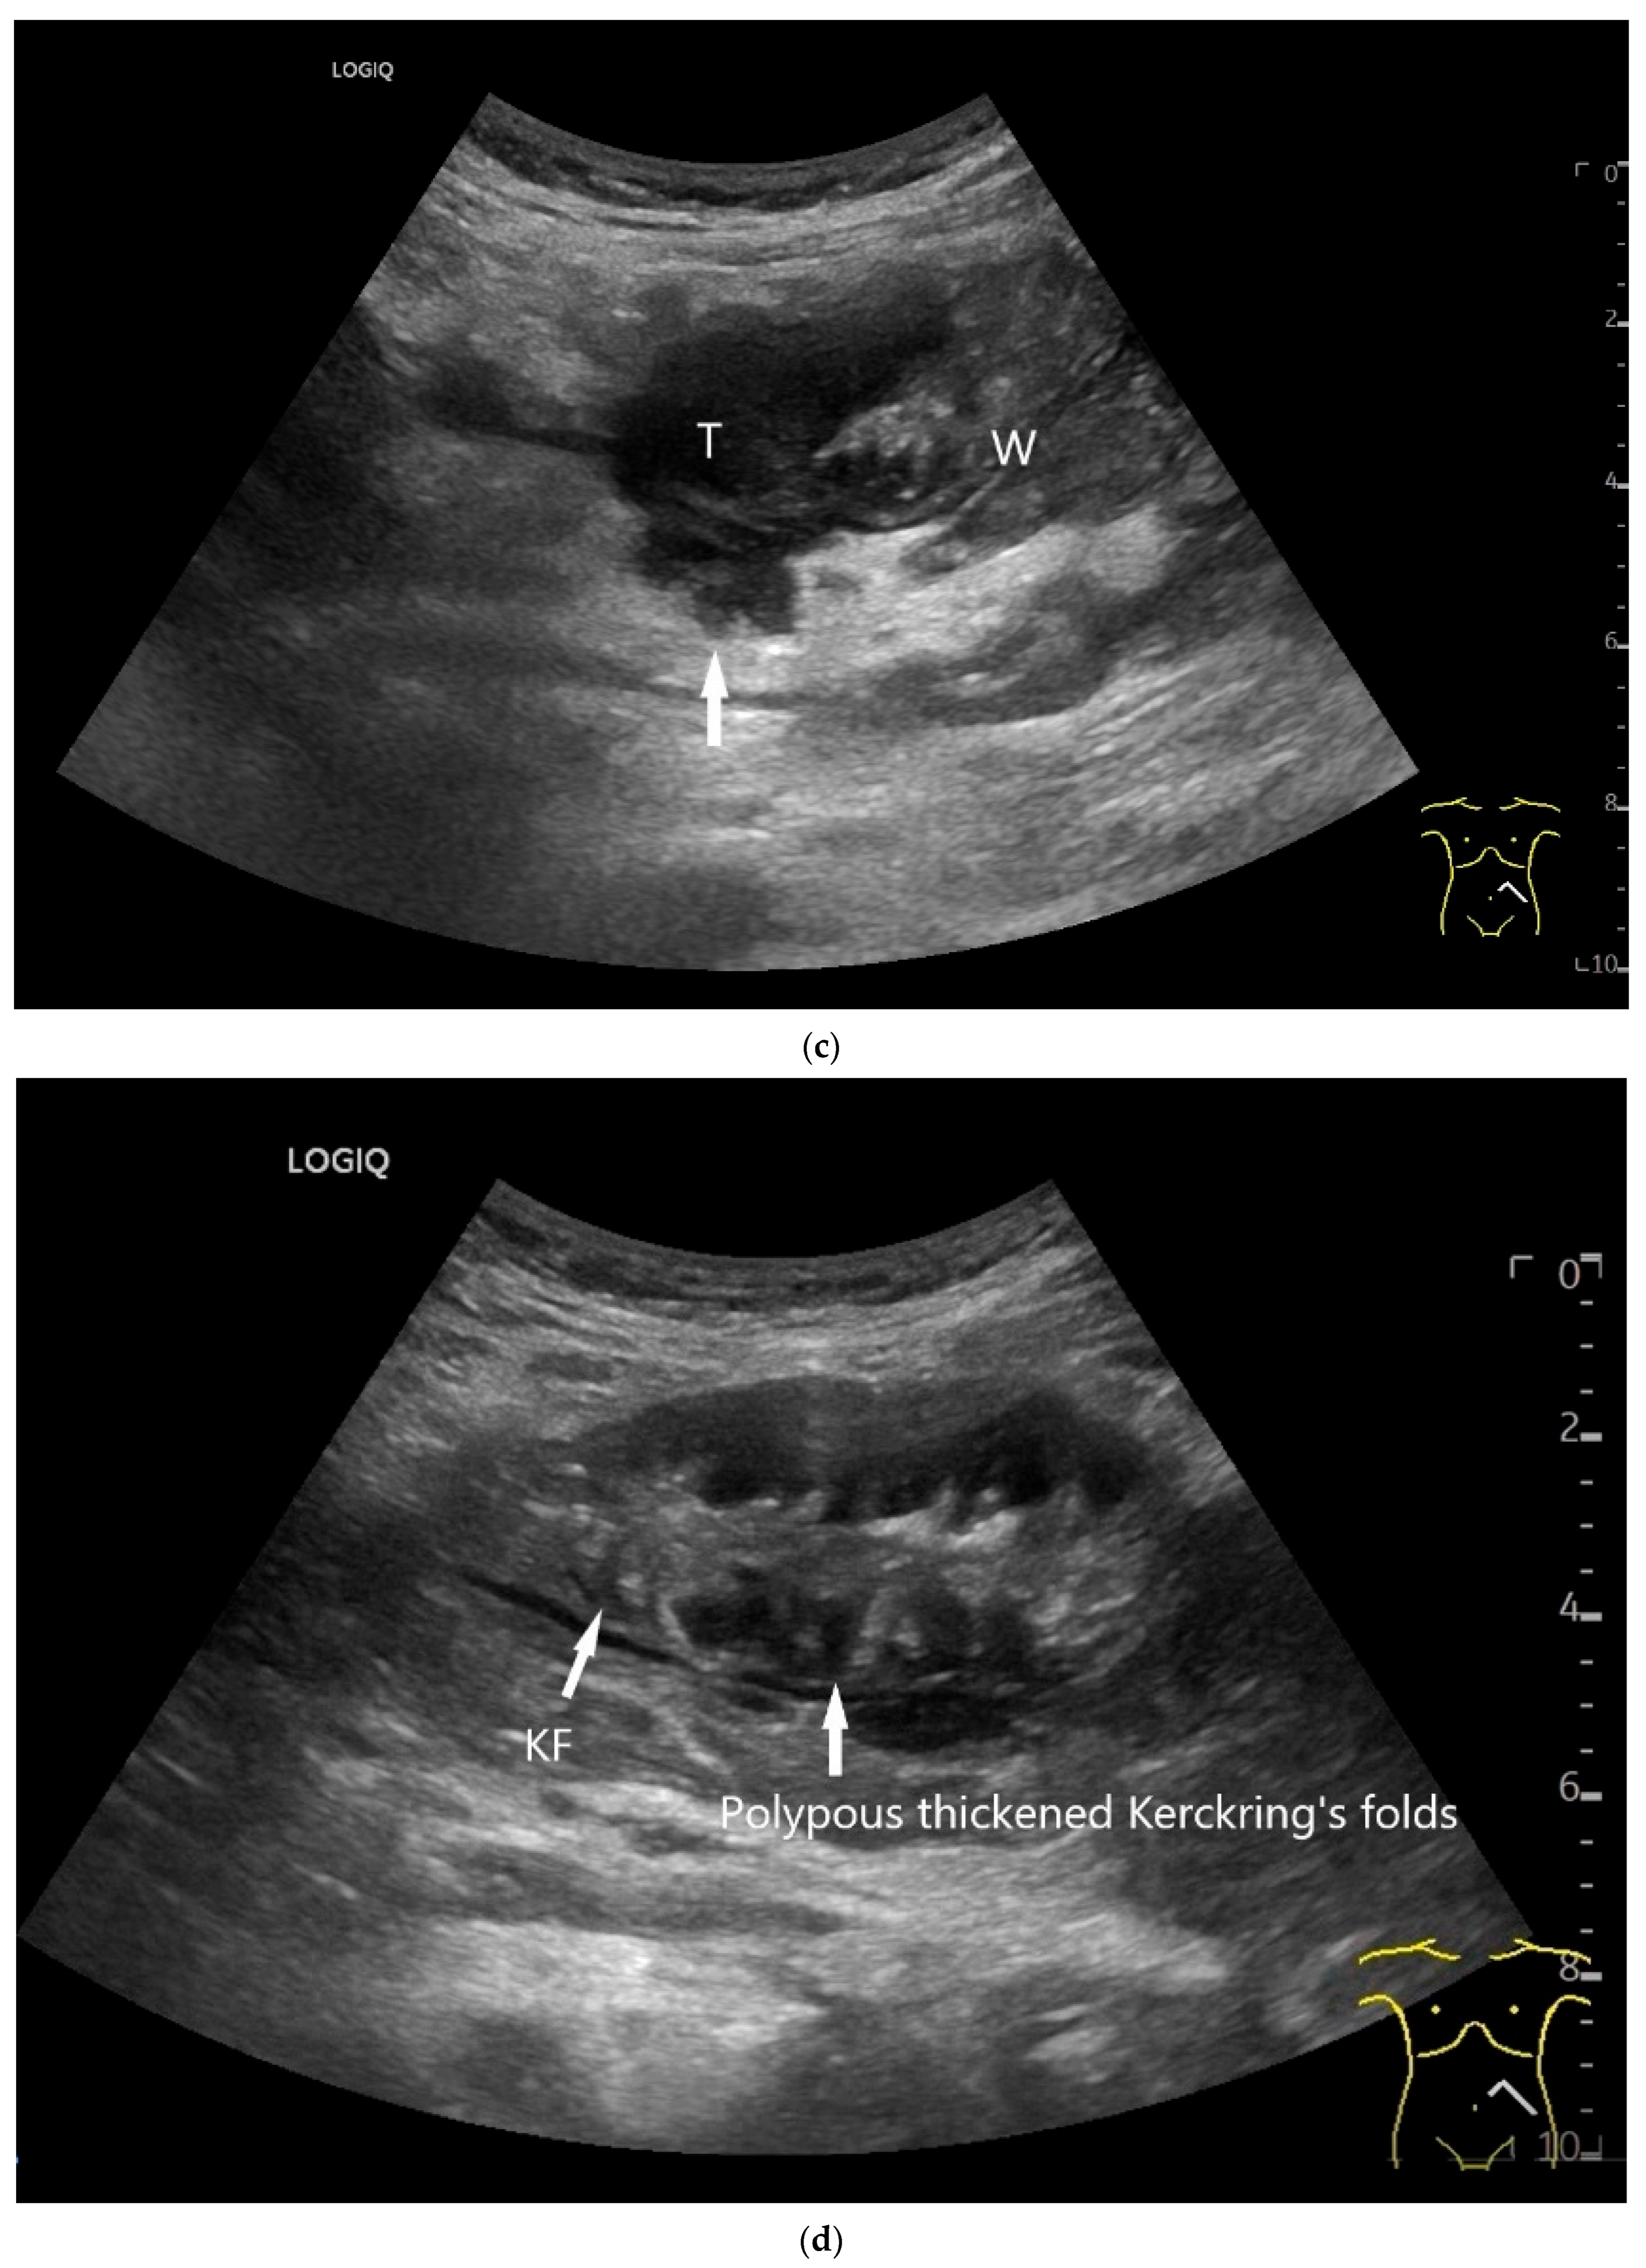

Ultrasound Imaging of Small Intestine NEN

| Neuroendocrine tumor | Small, nodular hypoechoic wall thickenings, mostly in the submucosa with spreading into the other layers. Usually with small vessels on CDI. Regionally enlarged lymph nodes. Multilocular manifestations are possible. |

| Lymphoma | Very pronounced wall thickening with marked hypoechogenicity. Large regional and distant lymph nodes. Look for splenic infiltration. Tumor vessels on CDI and hyperenhancement on CEUS. Heterogeneous hyperechogenicity of the mesentery with walling of the mesenteric vessels. Multiple localizations are possible. |

| GIST | Round hypoechoic masses, homogeneous or heterogeneous depending on size. They usually originate from the muscularis propria, which can be difficult to distinguish in US. Small vessels on CDI, hyperenhancement on CEUS. They move with the small intestine and can change position. |